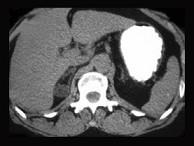

肾上腺皮质腺瘤患者,已行腺瘤切除术,术后使用可的松替代治疗的时间多为()A.1个月B.1~6个月C.6~12个月D.1~2年E.长期

问题 肾上腺皮质腺瘤患者,已行腺瘤切除术,术后使用可的松替代治疗的时间多为()

选项 A.1个月 B.1~6个月 C.6~12个月 D.1~2年 E.长期

答案 C